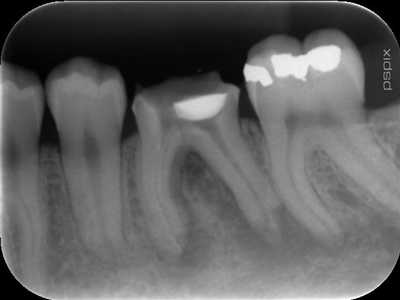

Le diagnostic radiologique des fêlures radiculaires dentaires est très difficile à faire, même pour les radiologues.

Je ne connais qu’un seul moyen de détecter une fêlure, c’est l’aspect radiologique de la lésion osseuse correspondante.

Cette lésion péri-radiculaire est dite « lésion en chaussette » et permet de faire le diagnostic certain d’une fêlure.

Il est bien évident, que l’apparition de nouvelles techniques d’imagerie telles que cône beam, 3D, Dentascan, ou scanner améliorent considérablement les possibilités de diagnostic des fêlures radiculaires. Mais la fêlure en elle même reste rarement visible, c’est l’aspect de la lyse osseuse engendrée par l’infiltration bactérienne ,qui reste déterminante pour le diagnostic.